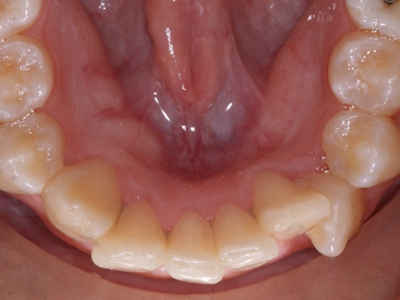

阻生牙是指由于邻牙、骨或软组织的阻碍而只能部分萌出或完全不能萌出,且以后也不能萌出的牙。引起牙阻生的成因,主要是由于颌骨缺乏足够的空间容纳全部恒牙。常见的阻生牙为下颌第三磨牙、上颌第三磨牙及上颌尖牙。

阻生牙可反复引起冠周炎,或引起邻牙牙根吸收和破坏,位置不正,不能完全萌出,好发部位是上、下颌第三磨牙。

阻生牙主要原因是随着人类的进化,颌骨的退化与牙量的退化不一致,导致骨量相对小于牙量,颌骨缺乏足够的空间容纳全部恒牙。